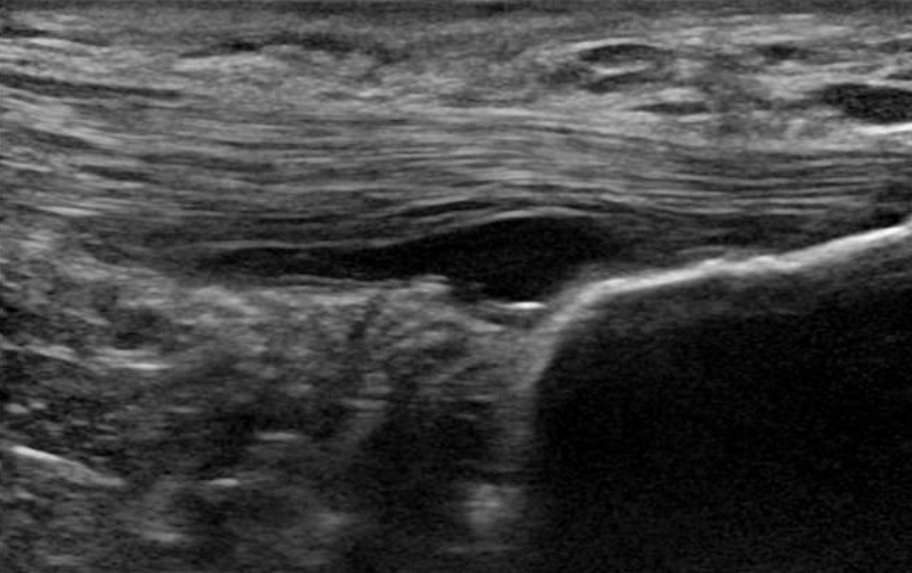

1. Se desconoce el motor nociceptivo del dolor en los tendones. La patología que se ve en las imágenes no es el motor del dolor. La vascularización no es el origen del dolor, sino simplemente un marcador de la degeneración del tendón. Además, no hay nervios sensoriales en la profundidad del tendón, sino en la periferia alrededor del mismo. Los nervios que crecen en un tendón patológico, son nervios simpáticos, no sensoriales. Por último, la sensibilización central es probablemente menos problemática en la patología de las extremidades inferiores en comparación con la de las superiores(Plinsinga et al. 2015, Plinsinga et al. 2018).

6. Un tendón patológico tiene más estructura que un tendón normal(Docking et al. 2015). Esto significa que podemos cargar estos tendones porque tenemos mucho tejido bueno. Las terapias para la patología de los tendones no son necesarias, porque de todas formas no podemos cambiar la estructura de la parte patológica. Por esta razón, Docking y sus colegas idearon la cita "Tratar el donut, no el agujero", es decir, centrarse en la estructura sana y no en la parte patológica.

Un tendón patológico tiene una estructura más buena que un tendón normal (Docking et al. 2015)